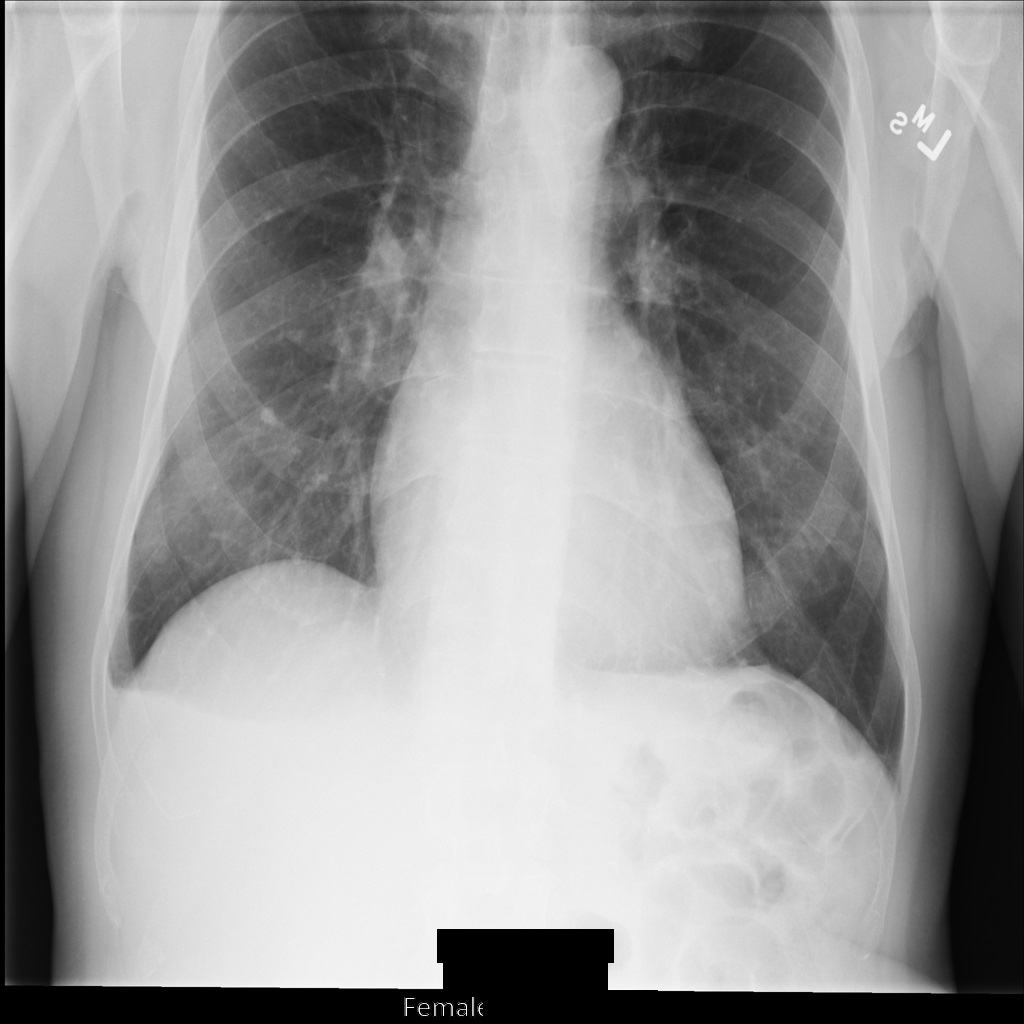

Après avoir anonymisé l'image à l'aide de REDACT_SENSITIVE_TEXT_CLEAN_DESCRIPTORS, elle se présente comme suit. Notez que tout le texte incrusté en bas de l'image n'a pas été masqué. Le texte Female s'affiche toujours, car PatientSex (0010,0040) ne fait pas partie des infoTypes DICOM par défaut.

REDACT_SENSITIVE_TEXT_CLEAN_DESCRIPTORS.Anonymiser des tags DICOM